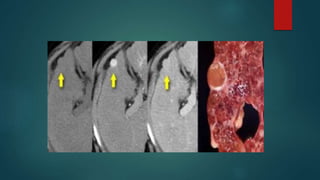

CT:

 Hypodense mass

 Central scar – Calcification

 Predominant heterogenous enhancement